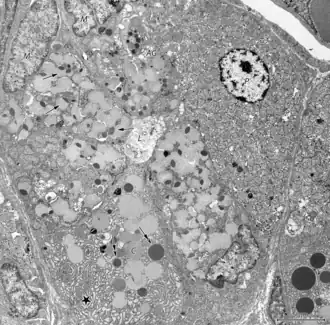

Slijmhalscellen, slijmnekcellen of muceuze nekcellen bevinden zich in de hals van de maagklieren, verspreid tussen de pariëtale cellen. Ze zijn zuilvormig of piramidaal met een basaal gelegen celkern. Ze zijn korter dan hun oppervlakte-tegenhangers en bevatten vesikels met kleinere hoeveelheden mucinekorrels aan de apicale kant. Het apicale oppervlak is bezet is met microvilli.

De slijmhalscellen van de maag kunnen histologisch worden onderscheiden van de slijmbekercellen, een ander type slijmafscheidende cel.